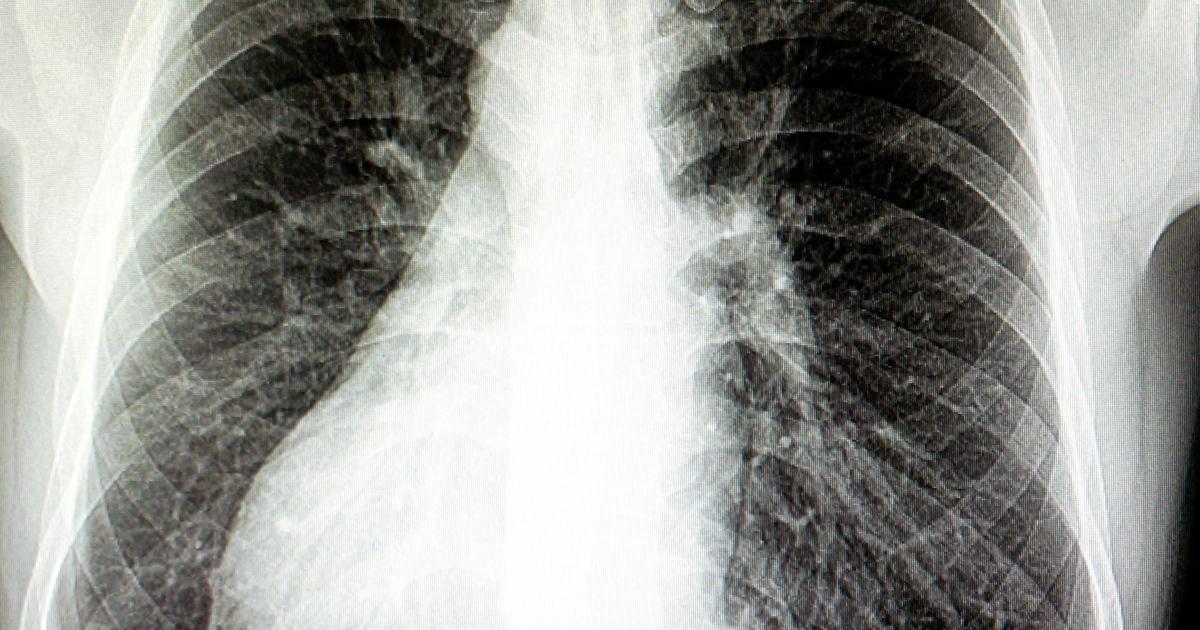

Situs Inversus

Situs inversus can be a symptom that occurs in individuals affected by nephronophthisis. Situs inversus is an anatomical abnormality where the internal organs in an individual are a mirror image of the normal anatomy. This abnormality means there is a full transposition of the internal organs with normal front to back symmetry. Nephronophthisis does not cause situs inversus, but they are both caused by mutations in some of the same genes. Mutations that occur the NPHP2 and INVS gene of chromosome 9q31, NPHP3 gene of chromosome 3q22, NPHP14 and ZNF423 gene of chromosome 16q12, or the NPHP16 and ANKS6 genes of chromosome 9q22 can cause an affected individual to have both situs inversus and nephronophthisis. Most cases involving situs inversus are the infantile variation of nephronophthisis where an individual is born with both conditions. Situs inversus associated with nephronophthisis is caused by a primary cilia dysfunction or primary ciliary dyskinesia that materializes during the patient's embryonic development.